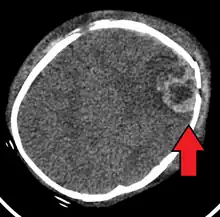

| An intraparenchymal bleed with overlying skull fracture from shaken baby syndrome | |

Diagnosis can be difficult as symptoms may be nonspecific.[1] A CT scan of the head is typically recommended if a concern is present.[1] It is unclear how useful subdural haematoma, retinal hemorrhages, and encephalopathy are alone at making the diagnosis.[25]

SBS may be misdiagnosed, underdiagnosed, and overdiagnosed,[28] and caregivers may lie or be unaware of the mechanism of injury.[15] Commonly, there are no externally visible signs of the condition.[15] Examination by an experienced ophthalmologist is critical in diagnosing shaken baby syndrome, as particular forms of ocular bleeding are strongly associated with AHT.[29] Magnetic resonance imaging may also depict retinal hemorrhaging[30] but is much less sensitive than an eye exam. Conditions that are often excluded by clinicians include hydrocephalus, sudden infant death syndrome (SIDS), seizure disorders, and infectious or congenital diseases like meningitis and metabolic disorders.[31][32] CT scanning and magnetic resonance imaging are used to diagnose the condition.[15] Conditions that often accompany SBS/AHT include classic patterns of skeletal fracturing (rib fractures, corner fractures), injury to the cervical spine (in the neck), retinal hemorrhage, cerebral bleed or atrophy, hydrocephalus, and papilledema (swelling of the optic disc).[16]